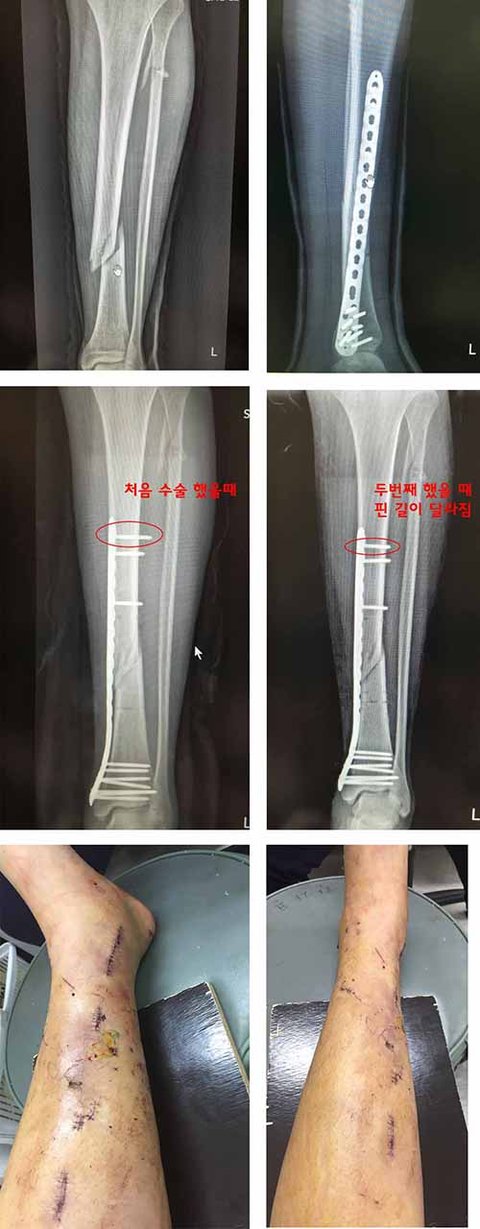

서울에서는 취직이 어려워 제주도의 한 농장에 일하러 갔는데 도착한 다음날 슬리퍼 신고 걷다가 빗길에 미끄러져서 다리가 골절 됐어요. (농장과는 무관한 사고)왼쪽 경골, 비골 모두 뿌러져서 구급차에 실려가 모 병원에서 응급수술을 받게 되었습니다.젊어보이는 의사였고 복숭아 뼈 옆에 수술자국이 생길거라 듣고 전신마취로 수술이 진행됐는데,의사가 제가 마취가 되서 의식이 없는 줄 알고 수술방에 있는 사람들한테"얘 제주도에 연고지도 없고 보호자도 없어. 아무것도 없으니 부담없이 편하게 해도 돼"이런 소리를 하는 걸 들었습니다.불안한 마음이 들었지만 마취가 되는 중이라 항의할 수 없었고,수술이 끝나서 엑스레이 찍고 병실에 왔는데 의사가 뛰어오더니...엑스레이 사진을 보여주면서 "크게 상관은 없는데 그냥 다시 합시다. 굳이 안해도 되긴 하는데 혹시 모르니까..." 이러면서 씨익 웃고 제 침대를 끌고 다시 수술방으로 데려갔습니다.

알고보니 의사가 핀을 잘못 박아서 핀을 교체하는거였고 환자 본인 동의도 없이 한번 더 전신마취를 하고 수술을 한거죠ㅡㅡ

그 결과... 다들 예상하셨겠지만..... 다리는 누가봐도 대충 수술한 것처럼 여기저기 수술자국으로 만신창이가 되있었고, 상처에서는 일주일이 지나도 피고름이 나왔습니다.의료사고임에도 병원비 삭감도 없었으며 수술이 잘되었으니 소개팅 해달라고 했습니다.

[※혐짤 주의※].....